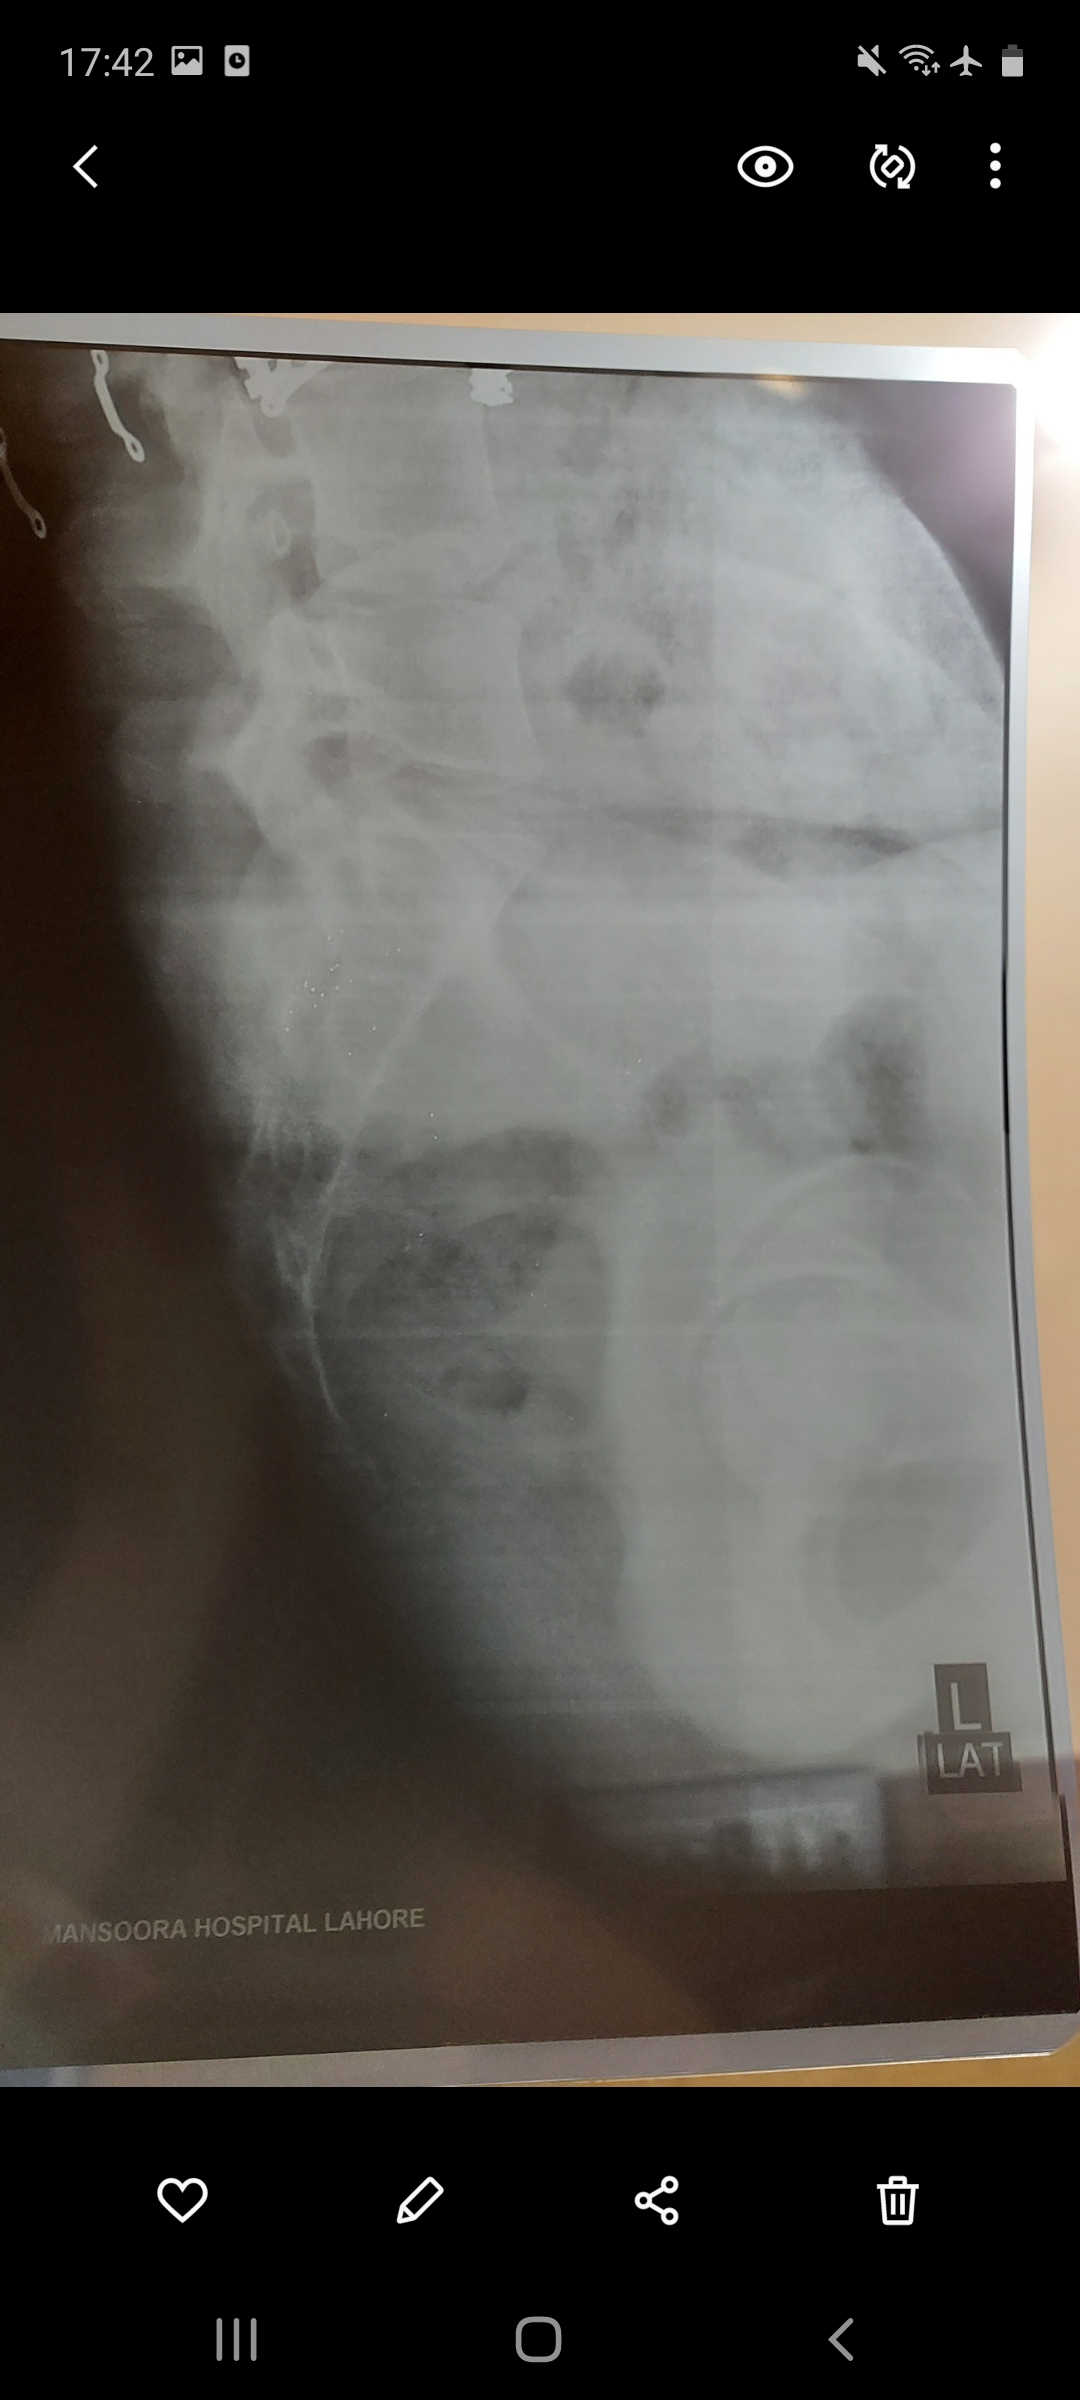

I have pain in my tail bone. Now I have when I sit or stand or lay on bed. Doc said its inflammation HISTORY--> tailbone was injured by falling 2 times at the same spot 5 years ago. I had that similar pain always while sitting or standing for long time but now it has increased n its very painful cant sit in my class. XRAY ATTACHED Thank you in advance